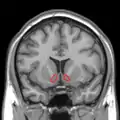

التصوير بالرنين المغناطيسي الشريحة الاكليلية تظهر النواة المتكئة المبينة باللون الأحمر